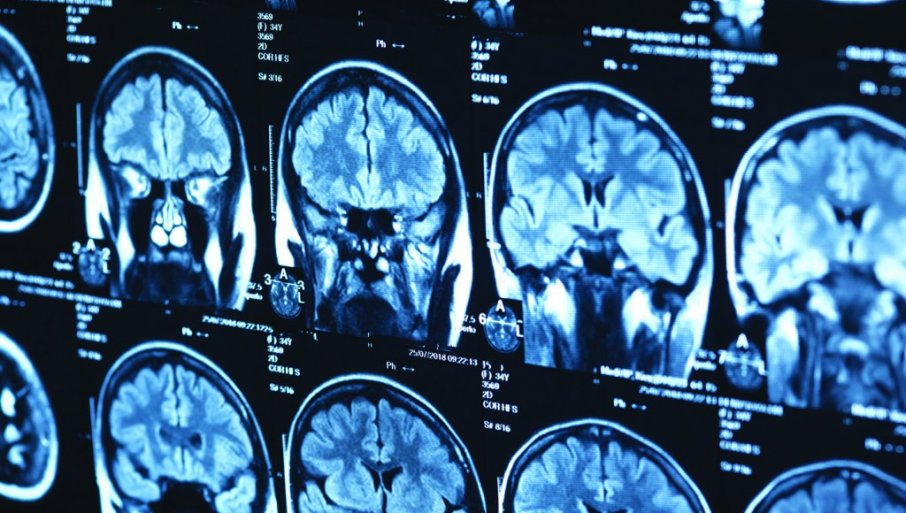

KORIŠĆENjE veštačke inteligenicije u određivanju vremena kada se dogodio moždani udar, moglo bi biti dvostruko tačnije od sadašnjih metoda koje se koriste. To bi značajno pomoglo lekarima u donošenju hitnih odluka o lečenju.